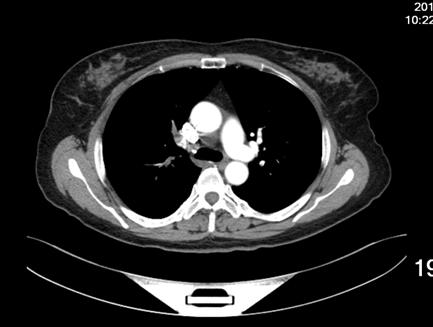

患者女性,52岁,因右膝关节疼痛,活动受限三十年入院。既往无高血压等慢性病史,无静脉血栓栓塞症病史,无慢性静脉瓣功能不全病史。诊断:右膝半月板损伤,骨关节炎。术前排除手术禁忌,于CSEA下行右膝关节镜下探查清理,半月板成形术。手术过程顺利,手术使用止血带,手术时间25分钟,失血约10ml。术后24小时患者下床后出现头晕、头迷、气短、冷汗、扶墙晕倒于墙边,给予心电血氧监护,血压:78/45mmHg,心率:118次/分,指脉血氧饱和度:78%,急检指尖血糖:6.4,血浆D-二聚体:1247ug/L,心肌酶谱及肌钙蛋白未见明显异常,术后2天夜晚再次出现头晕,头迷,气短,冷汗等症状,给予吸氧等治疗后症状缓解,检查肺增强CT(图1),示患者多发肺动脉栓塞,行双下肢静脉彩超检查,示右小腿肌间血栓,左小腿肌间静脉扩张(图2)。术后第3天于局麻下行经皮下腔静脉滤器置入术后,转入呼吸科行继续治疗。

1增强肺动脉CT:多发性肺动脉栓塞。